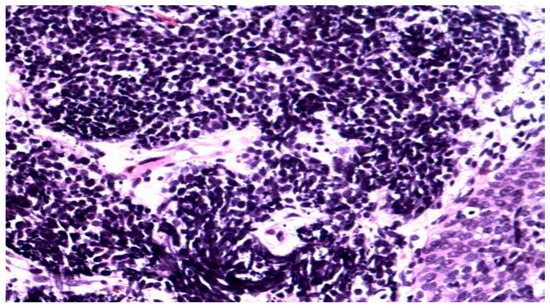

Background: Meningoencephalitis is a complex inflammatory condition of the CNS that can result in significant morbidity and mortality in critically ill adults. Accurate and timely neuromonitoring is essential for guiding management and improving outcomes. This study aimed to descriptively evaluate the prognostic value of early TCCD monitoring, particularly the pulsatility index, and its integration with conventional and perfusion MRI in patients with meningoencephalitis. Methods: We present an observational, retrospective, cohort study involving ten adult patients (median age 56 years, IQR 45.5–68.5; mean 55.9, range 35–76) with neurological syndromes caused by suspected or confirmed infectious meningoencephalitis. Etiologies included bacterial meningitis/meningoencephalitis (50%), viral meningoencephalitis (10%), neurotoxoplasmosis (10%), progressive multifocal leukoencephalopathy (10%), and undetermined origin (20%). Patients underwent TCCD and MRI within 24 h. In five cases, standard MRI sequences were acquired, while in the remaining five, perfusion imaging was performed using Arterial Spin Labelling (ASL). A favorable outcome was defined as survival with neurological recovery (Glasgow Outcome Scale > 5) at ICU discharge. Results: TCCD-derived PI provided valuable information on cerebral hemodynamics. PI values ≤ 1.25 were associated with favorable clinical outcomes and symmetrical MRI findings. Conversely, PI > 1.25 correlated with poor prognosis and often preceded MRI-detectable structural damage. When combined with ASL, PI mirrored the detected perfusion asymmetries and was associated with poor prognosis in fatal cases. Conclusions: Bedside TCCD can offer real-time assessment of cerebrovascular dynamics and, when integrated with conventional and ASL MRI, could enhance the understanding of pathophysiological processes in meningoencephalitis, supporting timely and informed decisions in neurocritical care.